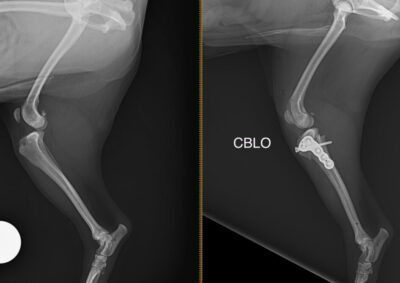

整形外科 注意 ボタンをクリックした先に、治療中および手術中の画像が説明で使用されている場合がございます。 そのような画像に弱い方は閲覧なさらないようお願いいたします。 整形外科 股関節脱臼に対するBUSTOR #65 整形外科 若齢犬の脛骨骨折 整形外科 橈尺骨固定術 #259 整形外科 膝蓋骨内方脱臼 G4 整形外科 膝蓋骨内方脱臼 G2~3 整形外科 橈骨固定術 #258 整形外科 膝蓋骨内方脱臼G3 整形外科 MPL G2 整形外科 CBLO #241 整形外科 膝蓋骨内方脱臼G3 整形外科 LCPDに対するFHNE 整形外科 CBLO#240 × Piezosurgery <12345678> 症例カテゴリー 放射線治療整形外科軟部組織外科脳神経外科内科腫瘍外科救急・集中治療リハビリテーション科腫瘍内科内視鏡科脳神経科呼吸器外科中医・漢方猫の腎移植循環器科